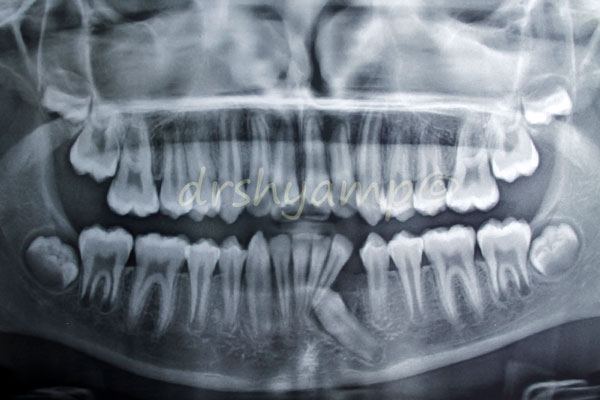

Disimpaction of Impacted canine